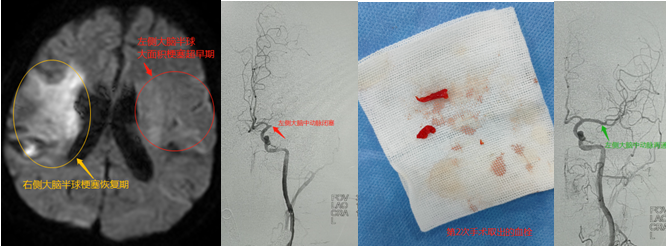

近期,海南省中医院脑病科二区救治1例一个多月内两次中风的患者,均快速取得满意疗效。患者为65岁女性,平时有房颤,未服药控制。第一次发生在今年224日,早上起床后家属发现患者口齿含糊,左侧肢体偏瘫,完全不能动。家属送至其他医院做完头颅CT后转到我院急诊,我院立即启动绿色通道,急查头颅MR提示“右侧大脑半球大面积急性梗塞、右侧颈内动脉闭塞”,本病极其凶险,如不及时开通血管,发病第2~3天会出现严重脑水肿危及生命,保守治疗病死率可达40%以上。脑病科二区团队经过评估,认为患者存在取栓意义。向家属解释病情,建议急诊取栓、挽救生命。患者家属听完后果断选择血管内治疗,接诊医生立即将患者从影像科转运至导管室手术。整个抢救过程高效、顺畅,从患者进入医院急诊科大厅到股动脉穿刺用时70分钟,远低于国家标准95分钟。上台造影证实右侧颈内动脉终末段闭塞,用可回收支架顺利取出血栓,血管完全再通。手术后第二天患者左侧上下肢就能快速抬起,康复科医生为患者安排了床边康复锻炼。10天后患者恢复良好,除反应稍差外,无其他后遗症。出院时叮嘱1个月时复查头颅CT,及时启动抗凝治疗。

遗憾的是,在出院后刚好1个月的当天晚上,患者饭后突发意识模糊,不能讲话,双眼不能向右看,右侧肢体瘫痪,完全不能动……有了上次经验,家属马上将患者送至我院急诊(不到半小时)。脑病科二区医生判断此次为血栓堵到了左边的大血管。家属豪不犹豫,马上选择再次行取栓术。同样的情节,同样的过程,从患者进入医院急诊科大厅到股动脉穿刺用时87分钟。手术中造影证实左侧大脑中动脉主干闭塞,用可回收支架取出血栓后血管完全再通。患者麻醉苏醒后右手就可以握医生的手了,力量还很大!第三天时患者可以讲话,眼球运动也灵活自如了。家属满意,医护安心!